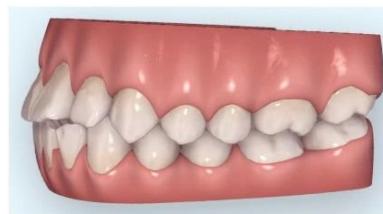

Intraoral examination revealed severe proclination and protrusion of both the maxillary and mandibular incisors [6]. The occlusal relationship was Class I at the canine (tooth 3) and first molar (tooth 6) levels bilaterally. A critical unfavorable biological factor was the proximity of the mandibular incisor roots to the labial cortical plate, representing a high-risk condition when planning extraction-based anterior retraction mechanics [10-12]. All four third molars were present.

Figure 2: Pre-Treatment Intraoral Photographs

Figure 3: Pre-Treatment Intraoral 3D Digital Models